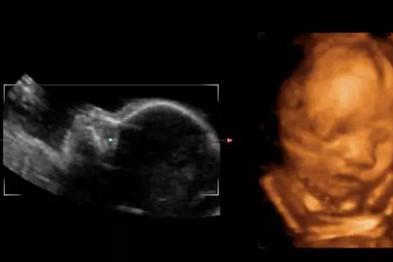

三維彩色多普勒超聲

——立體的照片

二維B超理解起來很簡單,大家掃過二維碼沒,叫二維碼就是因為它就是一張平面圖。所以二維B超看見的都是平面的圖案。

平面讓我們便于測量長度,立體讓我們看清楚邊邊角角,墻面玻璃。

因此實際在排畸的過程中,我們觀察內(nèi)臟,測量骨頭的長度用的還是二維的B超,只是在看皮膚表面(好像看墻的顏色和玻璃一樣)的時候才用三維。

所以所謂的三維或者四維排畸,都是結(jié)合二維來看的。這就是為什么我說二維排畸是完全夠用了,三維四維只能作為輔助,主要是看面部,手指和腳趾,以及給孩子留一張照片。

實時三維多普勒超聲(四維)

—— 會動的B超

四維比三維其實就是多了時間這一個維度,看見的寶寶是動態(tài)的,吃手啊,打嗝啊,伸懶腰啊,這些動作都可以看見。

所以也叫實時三維B超。

四維以外的B超,醫(yī)生看屏幕上的內(nèi)容都是一張張的截圖,所以看起來是不連貫的,四維看胎動是非常連貫的。

也就是說如果拍照三維就可以,如果需要視頻四維才可以,三維和四維的機(jī)器一般都是一個,同一個機(jī)器上探頭更換一下,屏幕切換一下就可以實現(xiàn)三維到四維的轉(zhuǎn)換。

所以如果你是想給寶寶錄下一段視頻,就需要做四維,如果只是為了排畸,三維結(jié)合二維已經(jīng)很完美了,二維排畸也是足夠的。